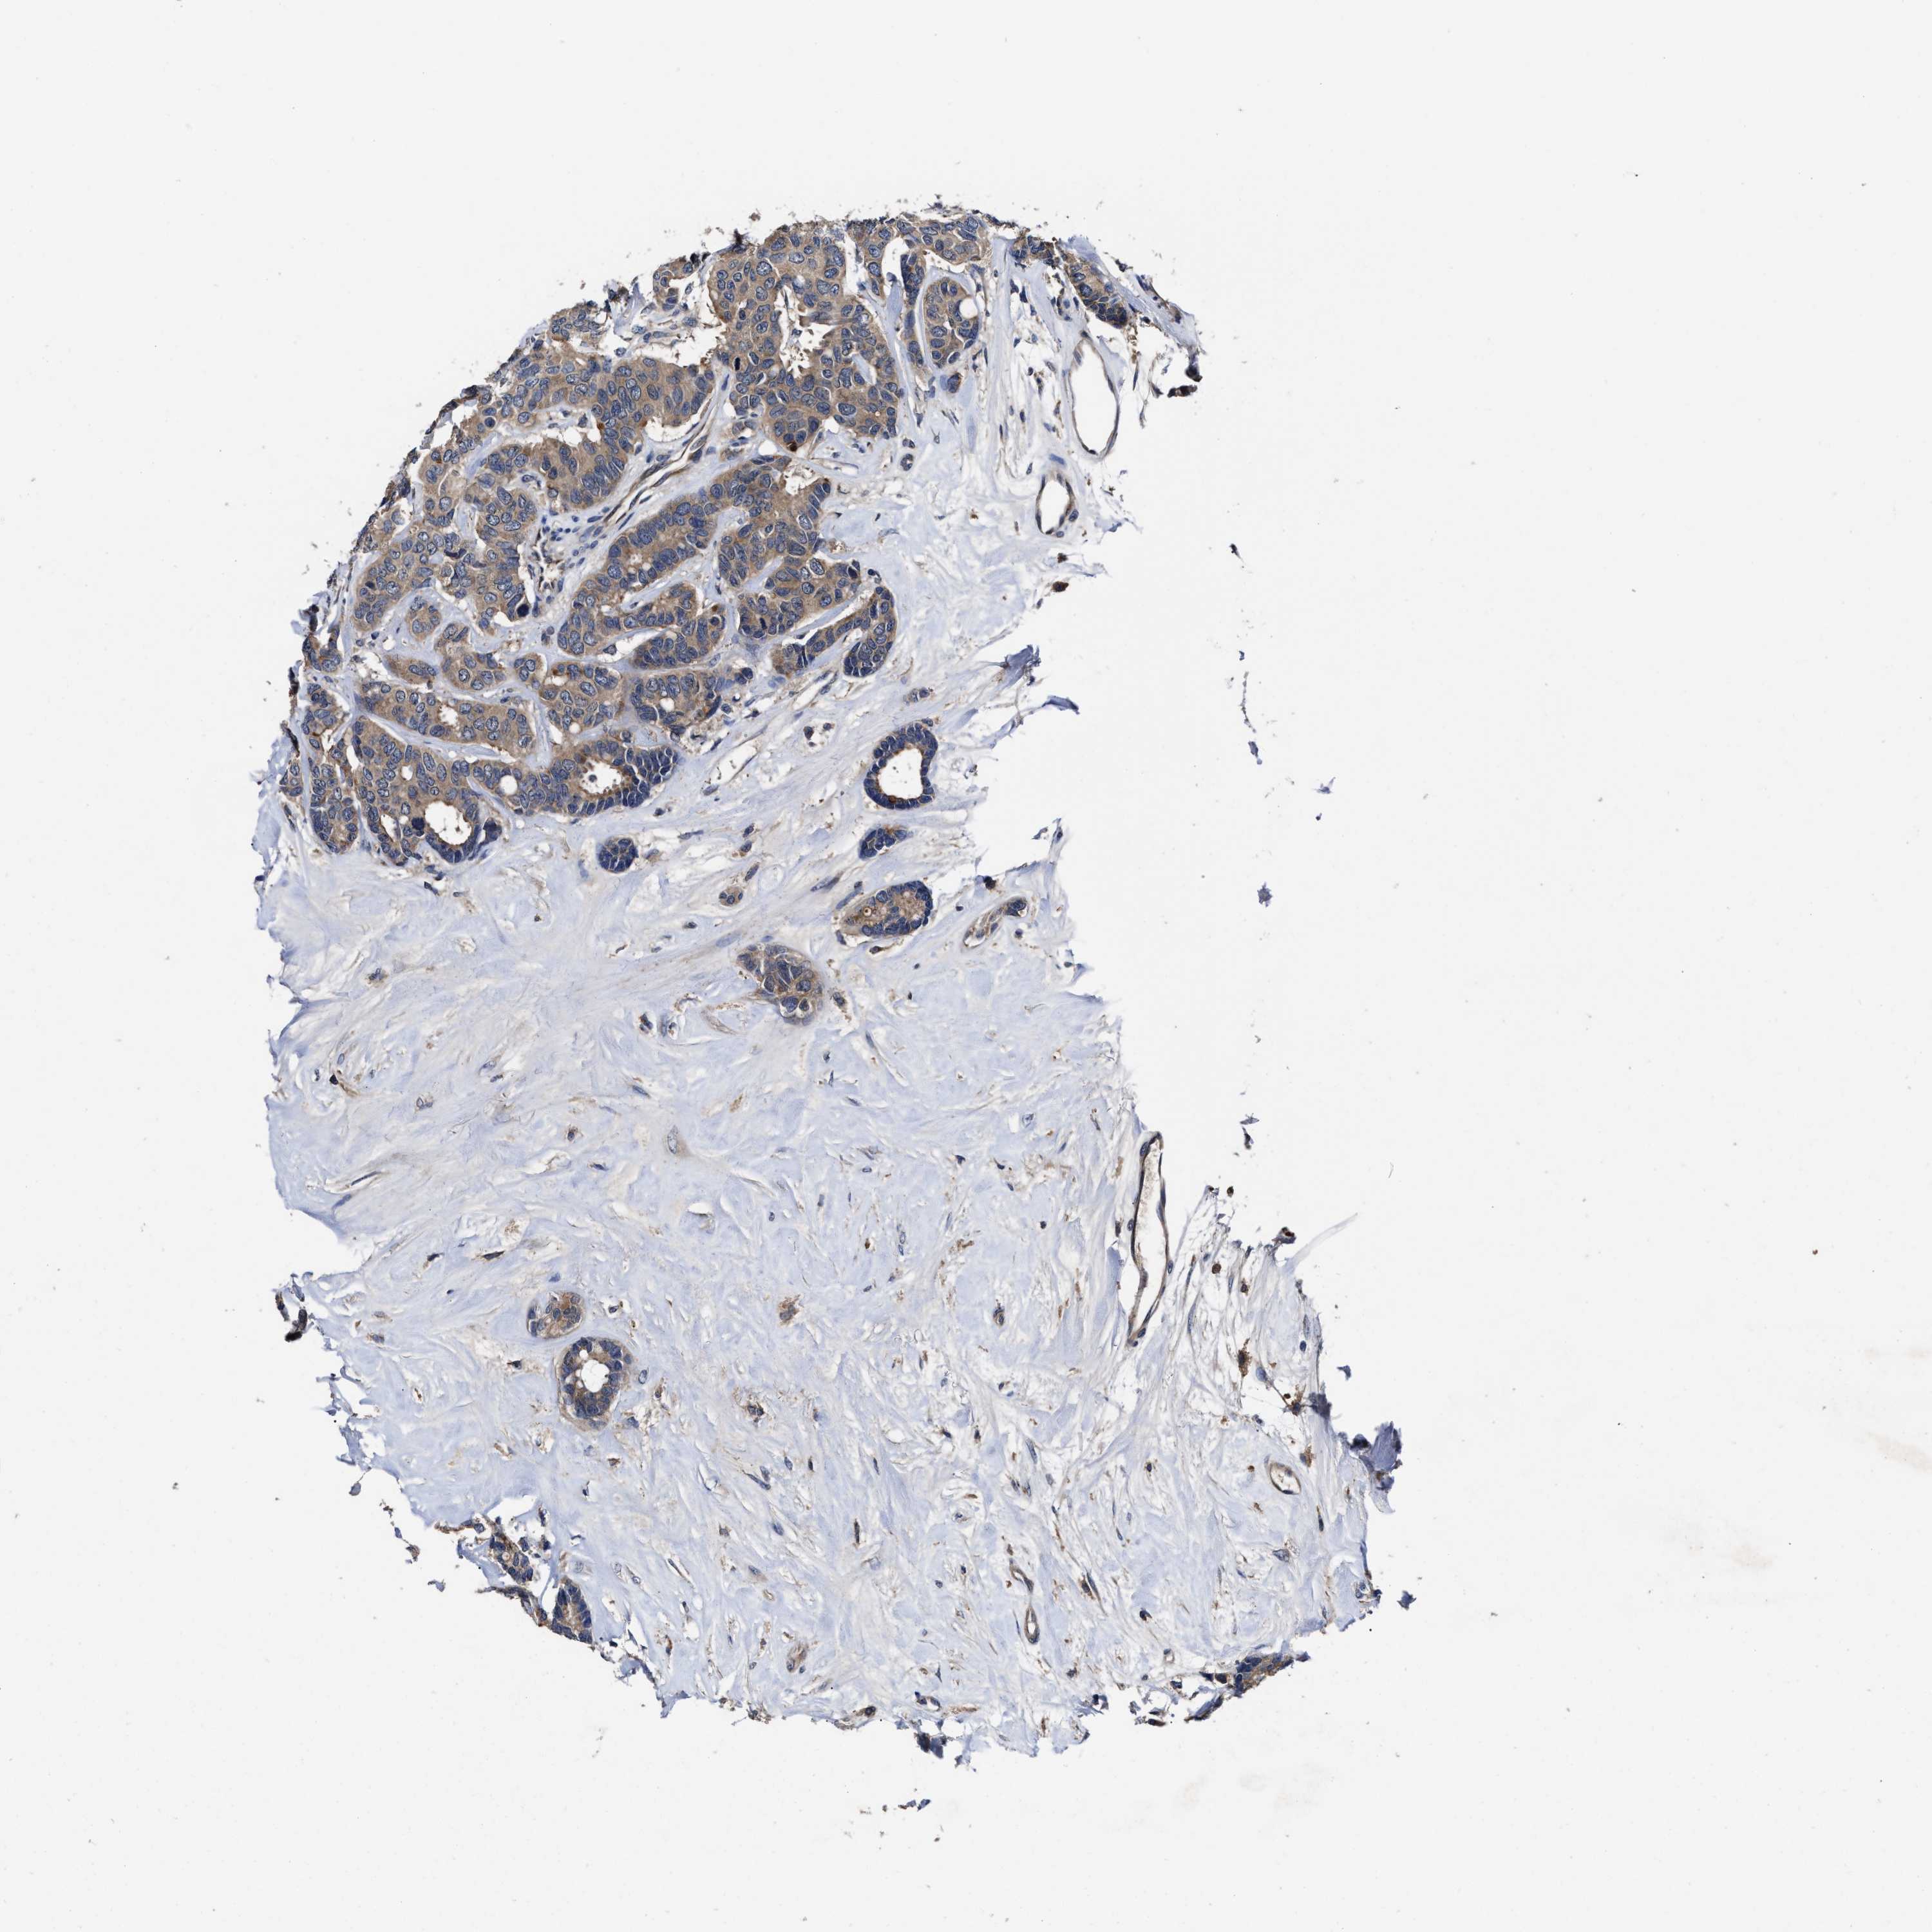

CANCER BREAST CANCER Show tissue menu

Breast cancer

Human cancer